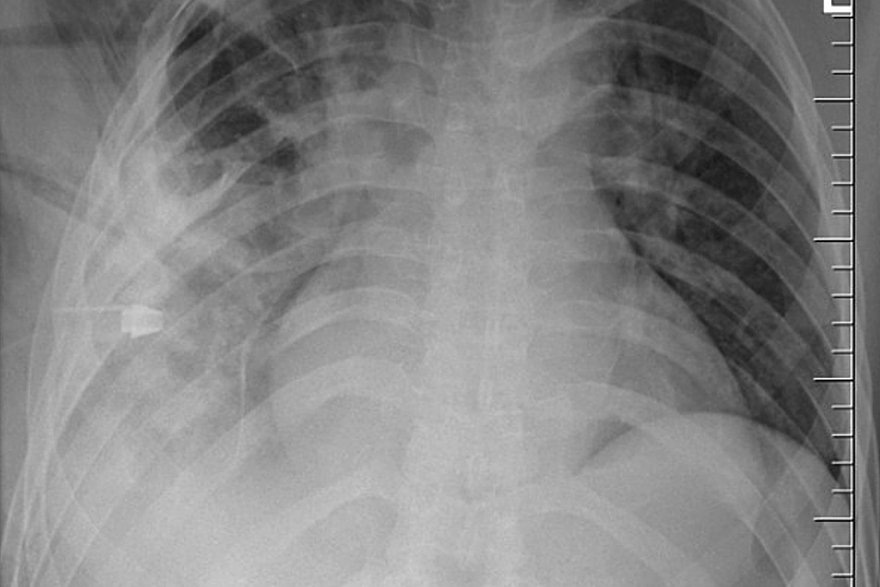

Фото: Journal of Surgical Case Reports

44-летний мужчина обратился в больницу из-за гнойных выделений в районе соска. Врачи удивились, что мужчина не жаловался на боли в груди, проблемы с дыханием и кашель, и сделали ему рентген. Тогда они и обнаружили, что внутри пациента застрял нож. Лезвие вошло рядом с правой лопаткой и не задело ни одного органа, поэтому он спокойно жил с ним.